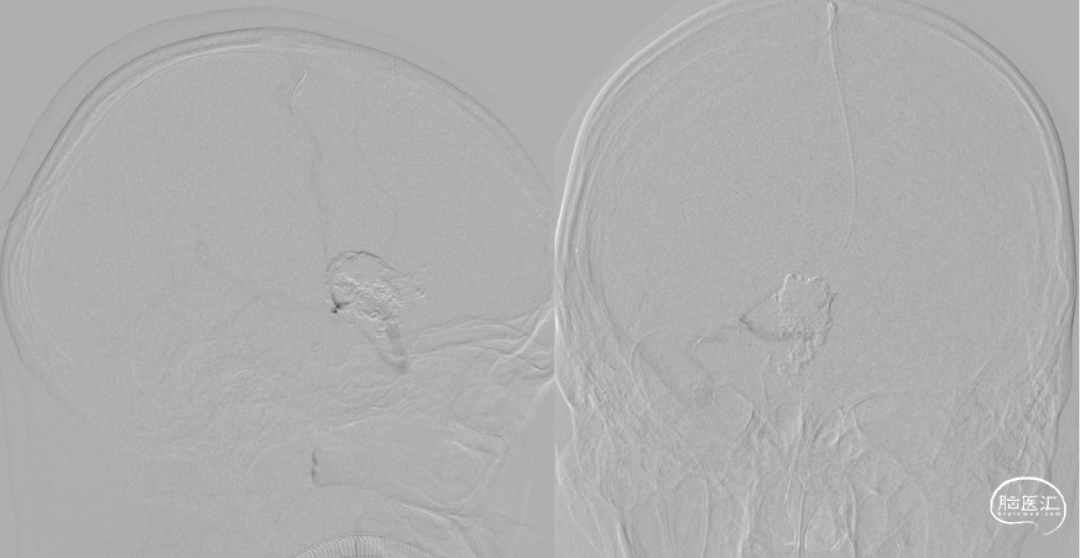

术后造影脑动静脉畸形消失

术后CT未见出血及梗塞